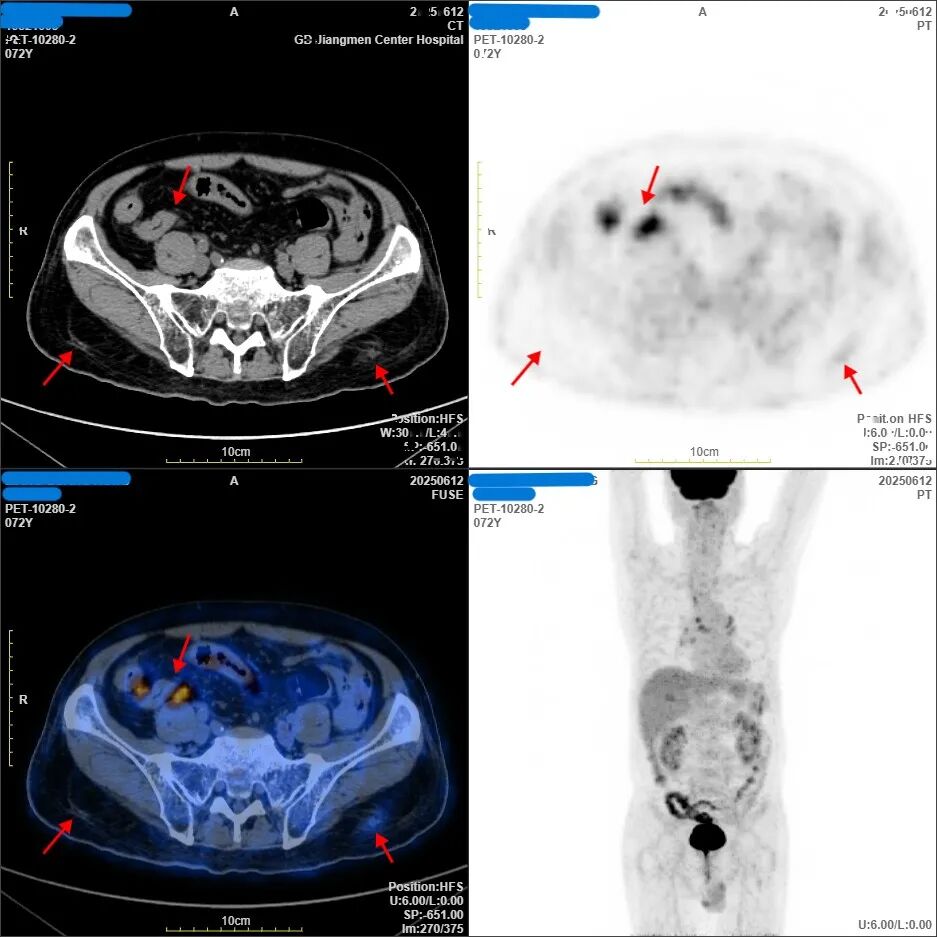

2025年1月,梁伯求诊于其他医院,PET-CT检查提示:全身多发淋巴结肿大,高代谢病灶(图中黑色斑点)已遍布全身,同时合并高血压、糖尿病等多种基础病。此时的梁伯面临的是高龄、高肿瘤负荷、多系统受侵的三重险境,这意味着肿瘤已不是“局部问题”,而是全身性、多系统的疾病,病情危重,治疗风险极高,梁伯与家人陷入困境.....

第一阶段:初始治疗时。病灶代谢高度活跃,疾病累及范围广(图中大面积明显亮斑/黑影)。最大病灶位于回盲部-阑尾,约8.9×6.5×9.6cm。

初战告捷:经过规范治疗,梁伯的症状率先迎来转机——咽痛吞咽困难迅速缓解,恢复正常进食。2025年6月复查PET-CT显示,肿瘤病灶明显缩小,代谢活性大幅抑制,疗效评估达到“部分缓解(PR)”。这极大鼓舞了梁伯战胜肿瘤的信心。

第二阶段:6周期结束后。对比初始影像,病灶范围已明显偏小,代谢活性显著下降,红色箭头标注处显示残留病灶正在减少。